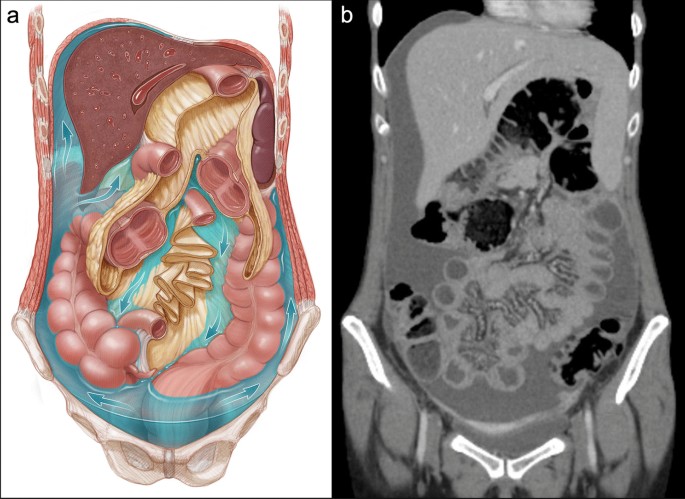

Peritoneal Cavity Vs Abdominal Cavity

Peritoneal vs Abdominal Cavities: Dissecting the Difference – Knya The Peritoneal Cavity - Greater Sac - Lesser Sac - TeachMeAnatomy Peritoneum Anatomy, Peritoneal Cavity, Retroperitoneal Organs ... Abdominal cavity - Wikipedia Definition of peritoneal cavity - NCI Dictionary of Cancer Terms - NCI Peritoneal Cavity Vs Abdominal Cavity